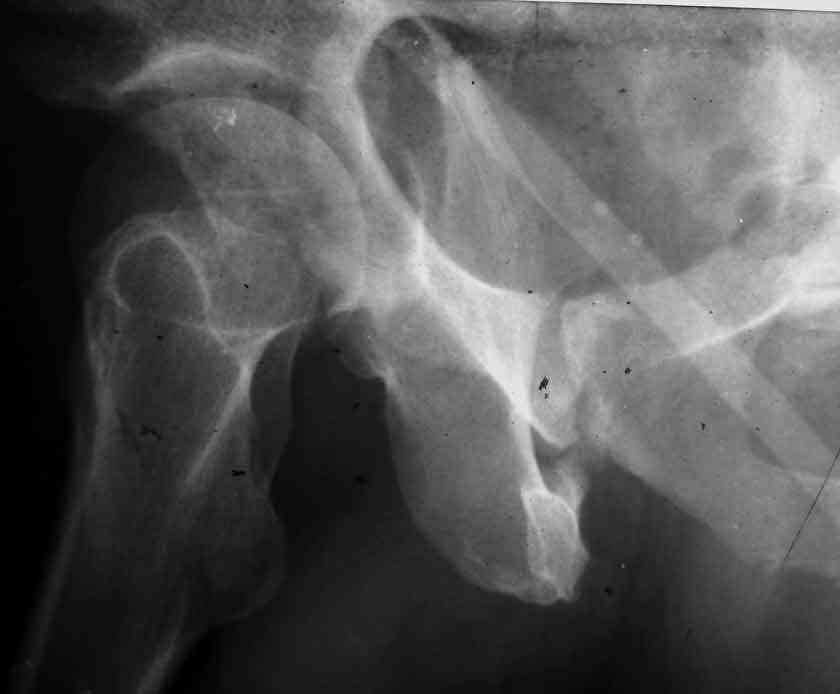

Dear Friends This is a 57 y old male.

Your input is welcome as to the classification of this fratcure, as well as the proposed management.

Dear Sir it looks quite difficult classify this fracture because the iliac view is not so clear.

In my opinion it is a column fracture because the obturator foramen is interrupted. There is a fracture of the posterior wall. If we assume the ap view as an iliac view it could be an anterior comun fracture plus posterior wall. It is difficult also to judge the head of the femur.

From the x rays it appears like a bicolumnar fracture with iliac extension (AO C1).